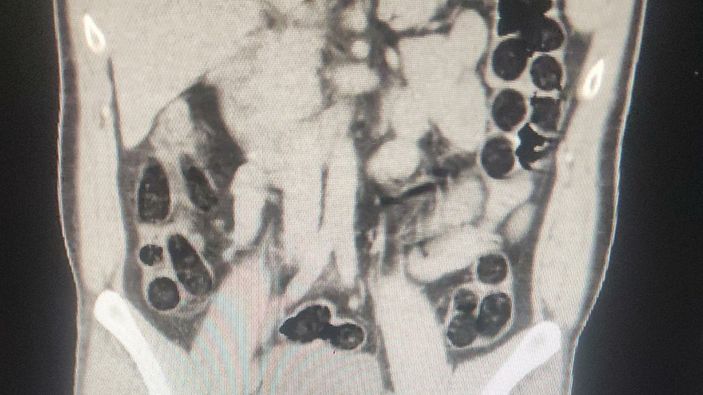

Midesinden eroin çıktı

Hastanede çekilen röntgenlerinde birinin midesinde uyuşturucu tespit edildi. Şüphelinin, 76 paket halinde 714 gram eroini doğal yollarla çıkarılması sağlandı.